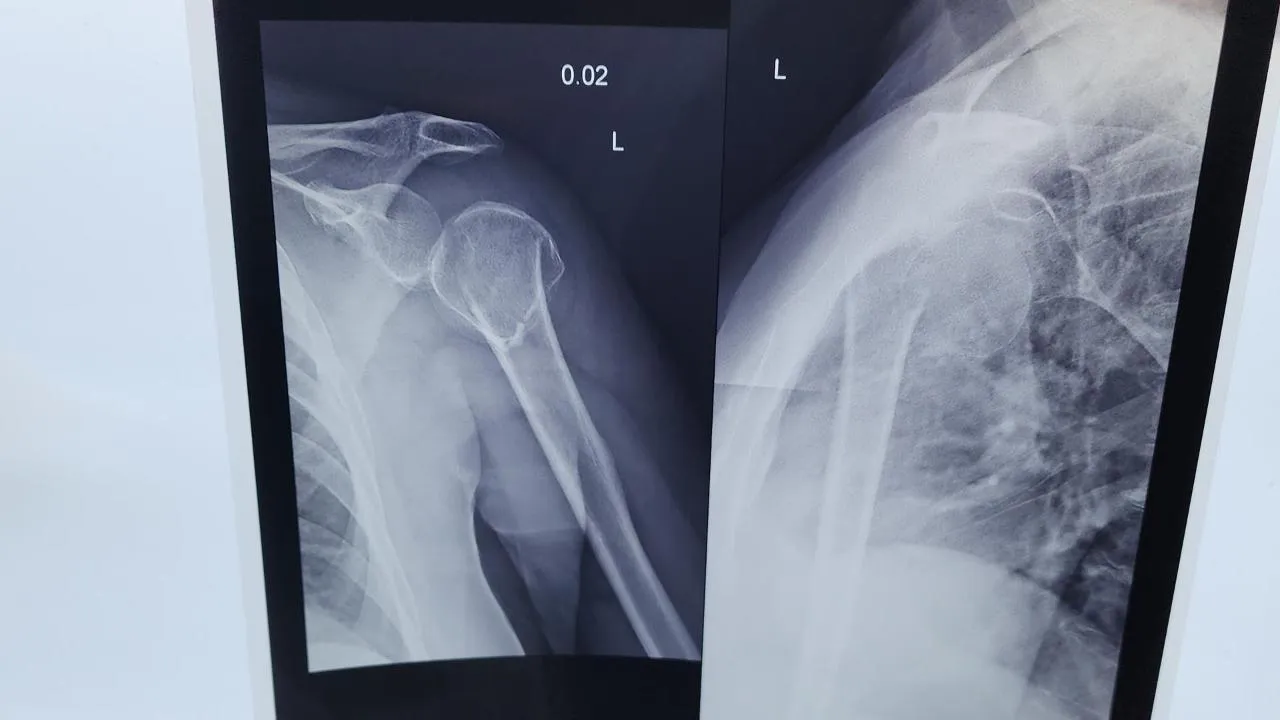

Врачи Красногорской больницы сделали пациентке реверсивное эндопротезированиеПациента поступила в Красногорскую клиническую больницу с серьезным диагнозом — полиостеоартроз, тяжелая III–IV стадия.

Женщину мучили выраженные боли и практически полное ограничение движений в плечевом суставе. Она уже перенесла несколько серьезных операций, у нее диагностировали системные заболевания, множественное поражение крупных суставов.

Единственным способом вернуть качество жизни стало реверсивное эндопротезирование плечевого сустава — высокотехнологичная операция, которая в Подмосковье выполняется единично.

Операцию пациентке провел врач травматолог-ортопед, кандидат медицинских наук, специалист с 27-летним хирургическим стажем Григорий Карапетян. Ежегодно он выполняет более 300 ортопедических операций, специализируется на протезировании суставов верхних и нижних конечностей.